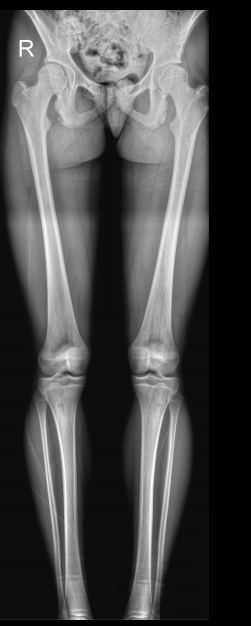

Из-за вертикального положения тела и необходимости перемещения на ногах именно на них приходится основная нагрузка. В результате нижние конечности имеют сложное строение, в котором важную роль играет взаимное расположение и пространственная ориентация отдельных элементов и сегментов. Для оценки движения в суставах, а также для планирования лечения разработаны референтные линии и углы, для определения которых используется длинномерная рентгенограмма или стичинг (Stitching). Это несколько прицельных снимков отдельных участков ног, собранные в один на экране компьютера.

С помощью стичинга на длинномерных снимках можно определить:

• Референтные линии и углы;

• Длину отдельных костей;

• Разницу в длине между правой и левой одноименными костями;

• Расстояние между идентичными точками на правой и левой ногах (при определении значения варусной и вальгусной деформации)

Подготовка не нужна. Для диагностики необходимо снять одежду с нижней половины туловища, оставаясь в белье, надеть защитный фартук и встать спиной к детектору. Стопы и коленные чашечки должны смотреть прямо, руки надо убрать за голову. Каждый раз рентгенолаборант помогает занять правильное положение. Если у пациента одна нога короче, подставляет под нее небольшую подставку.

Выполняется 3 снимка ног, включая таз, в прямой проекции, вам при этом не надо ничего делать. В некоторых случаях дополнительно требуются снимки в боковой проекции, при этом есть варианты: